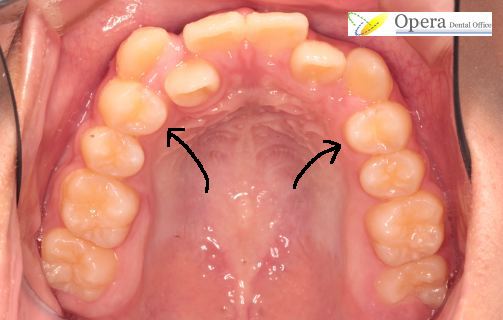

上あご咬合面観です。

上あごは奥歯が左右1本ずつ足りません。

しかし20歳頃親知らずが生えてきて、歯並びが完成します。